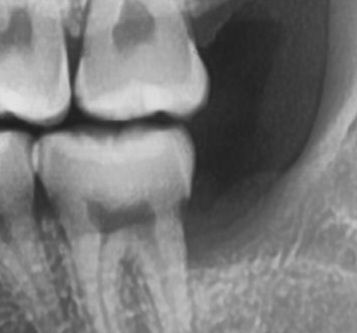

매복 사랑니 발치 후 어금니 패임 전후 사진 다시 올립니다

매복 사랑니 발치 미루다가 뽑았는데 앞 어금니 옆면이 사진처럼 각지고 부자연스럽게 패였습니다

전후 사진인데

• 1번 째 사진

치과의 실수로 해당 모양으로 된 것으로 보이진 않고 치아를 발치 한 후 겹친 모양이 드러난 것으로 보입니다.

• 사랑니가 기울어져 났을 경우에 사랑니가 걸려 있는 부위에 이물질이 남아 있게 되면 충치가 생기게 되고 사진처럼 각진 모양을 보일 수 있습니다 크게 문제가 되지 않기 때문에 걱정하지 않으셔도 되나 불편감이 있다면 해당 부위에 충치를 치료할 수 있습니다 자세한 확인을 위해서 치과에서 진료를 받아 보는 것을 권해 드립니다

• 손상이 일어날 정도로 겹쳐있진 않고 다만 사랑니와 어금니 틈 사이가 관리가 어려웠어서 충치가 생겨있는 것 같습니다 다만 해당부위는 깔끔하게 치료하기는 쉽지 않습니다 오히려 증상이 없다면 지켜보면서 관리를 잘해주는 것이 좋을 수도 있습니다